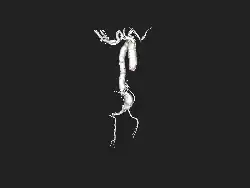

![]() | |

| Angiography of an aneurysm in a brain artery. The aneurysm is the large bulge in the center of the image. | |

An aneurysm is an outward bulging, likened to a bubble or balloon, caused by a localized, abnormal, weak spot on a blood vessel wall.[1] Aneurysms may be a result of a hereditary condition or an acquired disease. Aneurysms can also be a nidus (starting point) for clot formation (thrombosis) and embolization. As an aneurysm increases in size, the risk of rupture increases, which could lead to uncontrolled bleeding.[2] Although they may occur in any blood vessel, particularly lethal examples include aneurysms of the circle of Willis in the brain, aortic aneurysms affecting the thoracic aorta, and abdominal aortic aneurysms. Aneurysms can arise in the heart itself following a heart attack, including both ventricular and atrial septal aneurysms. There are congenital atrial septal aneurysms, a rare heart defect.